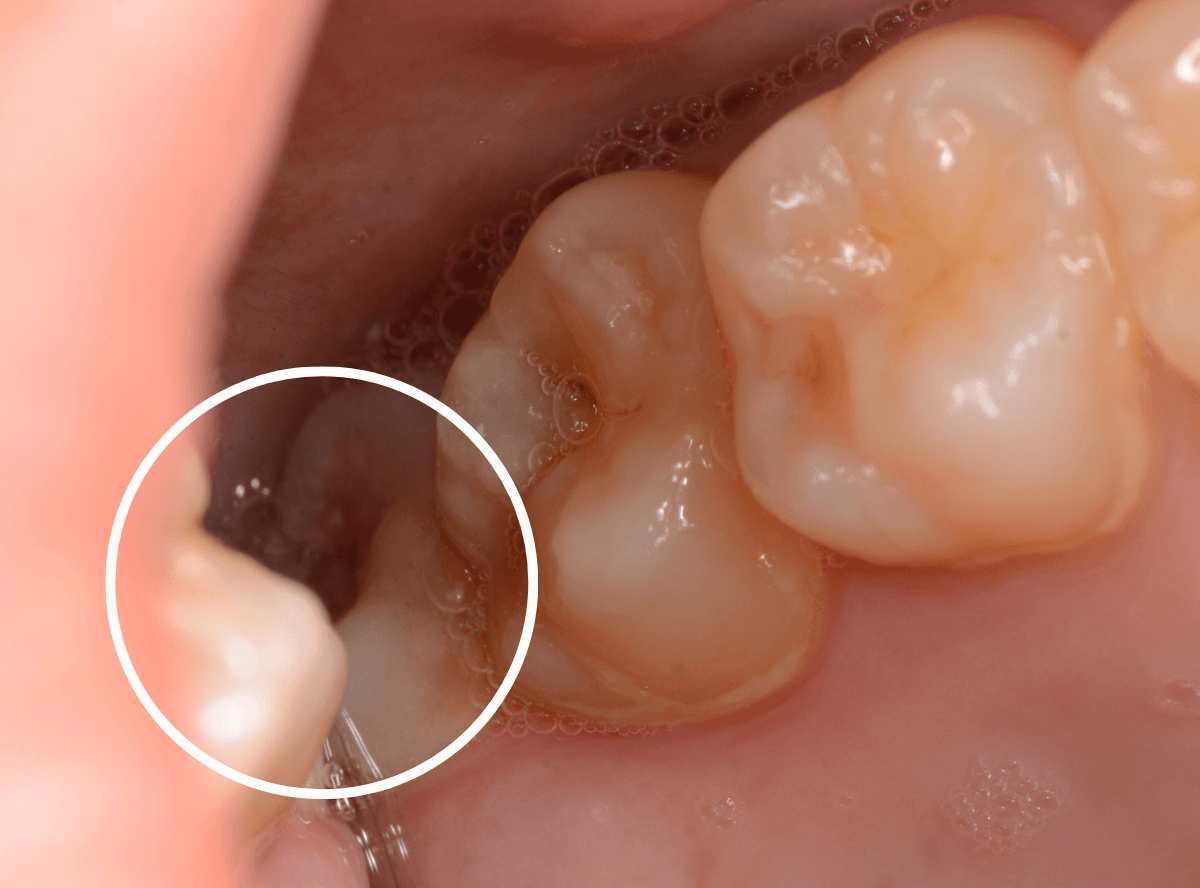

ここでは、比較的簡単なおやしらずの抜歯の例を中心にご紹介します。

このようなおやしらず、あなたはありませんか?